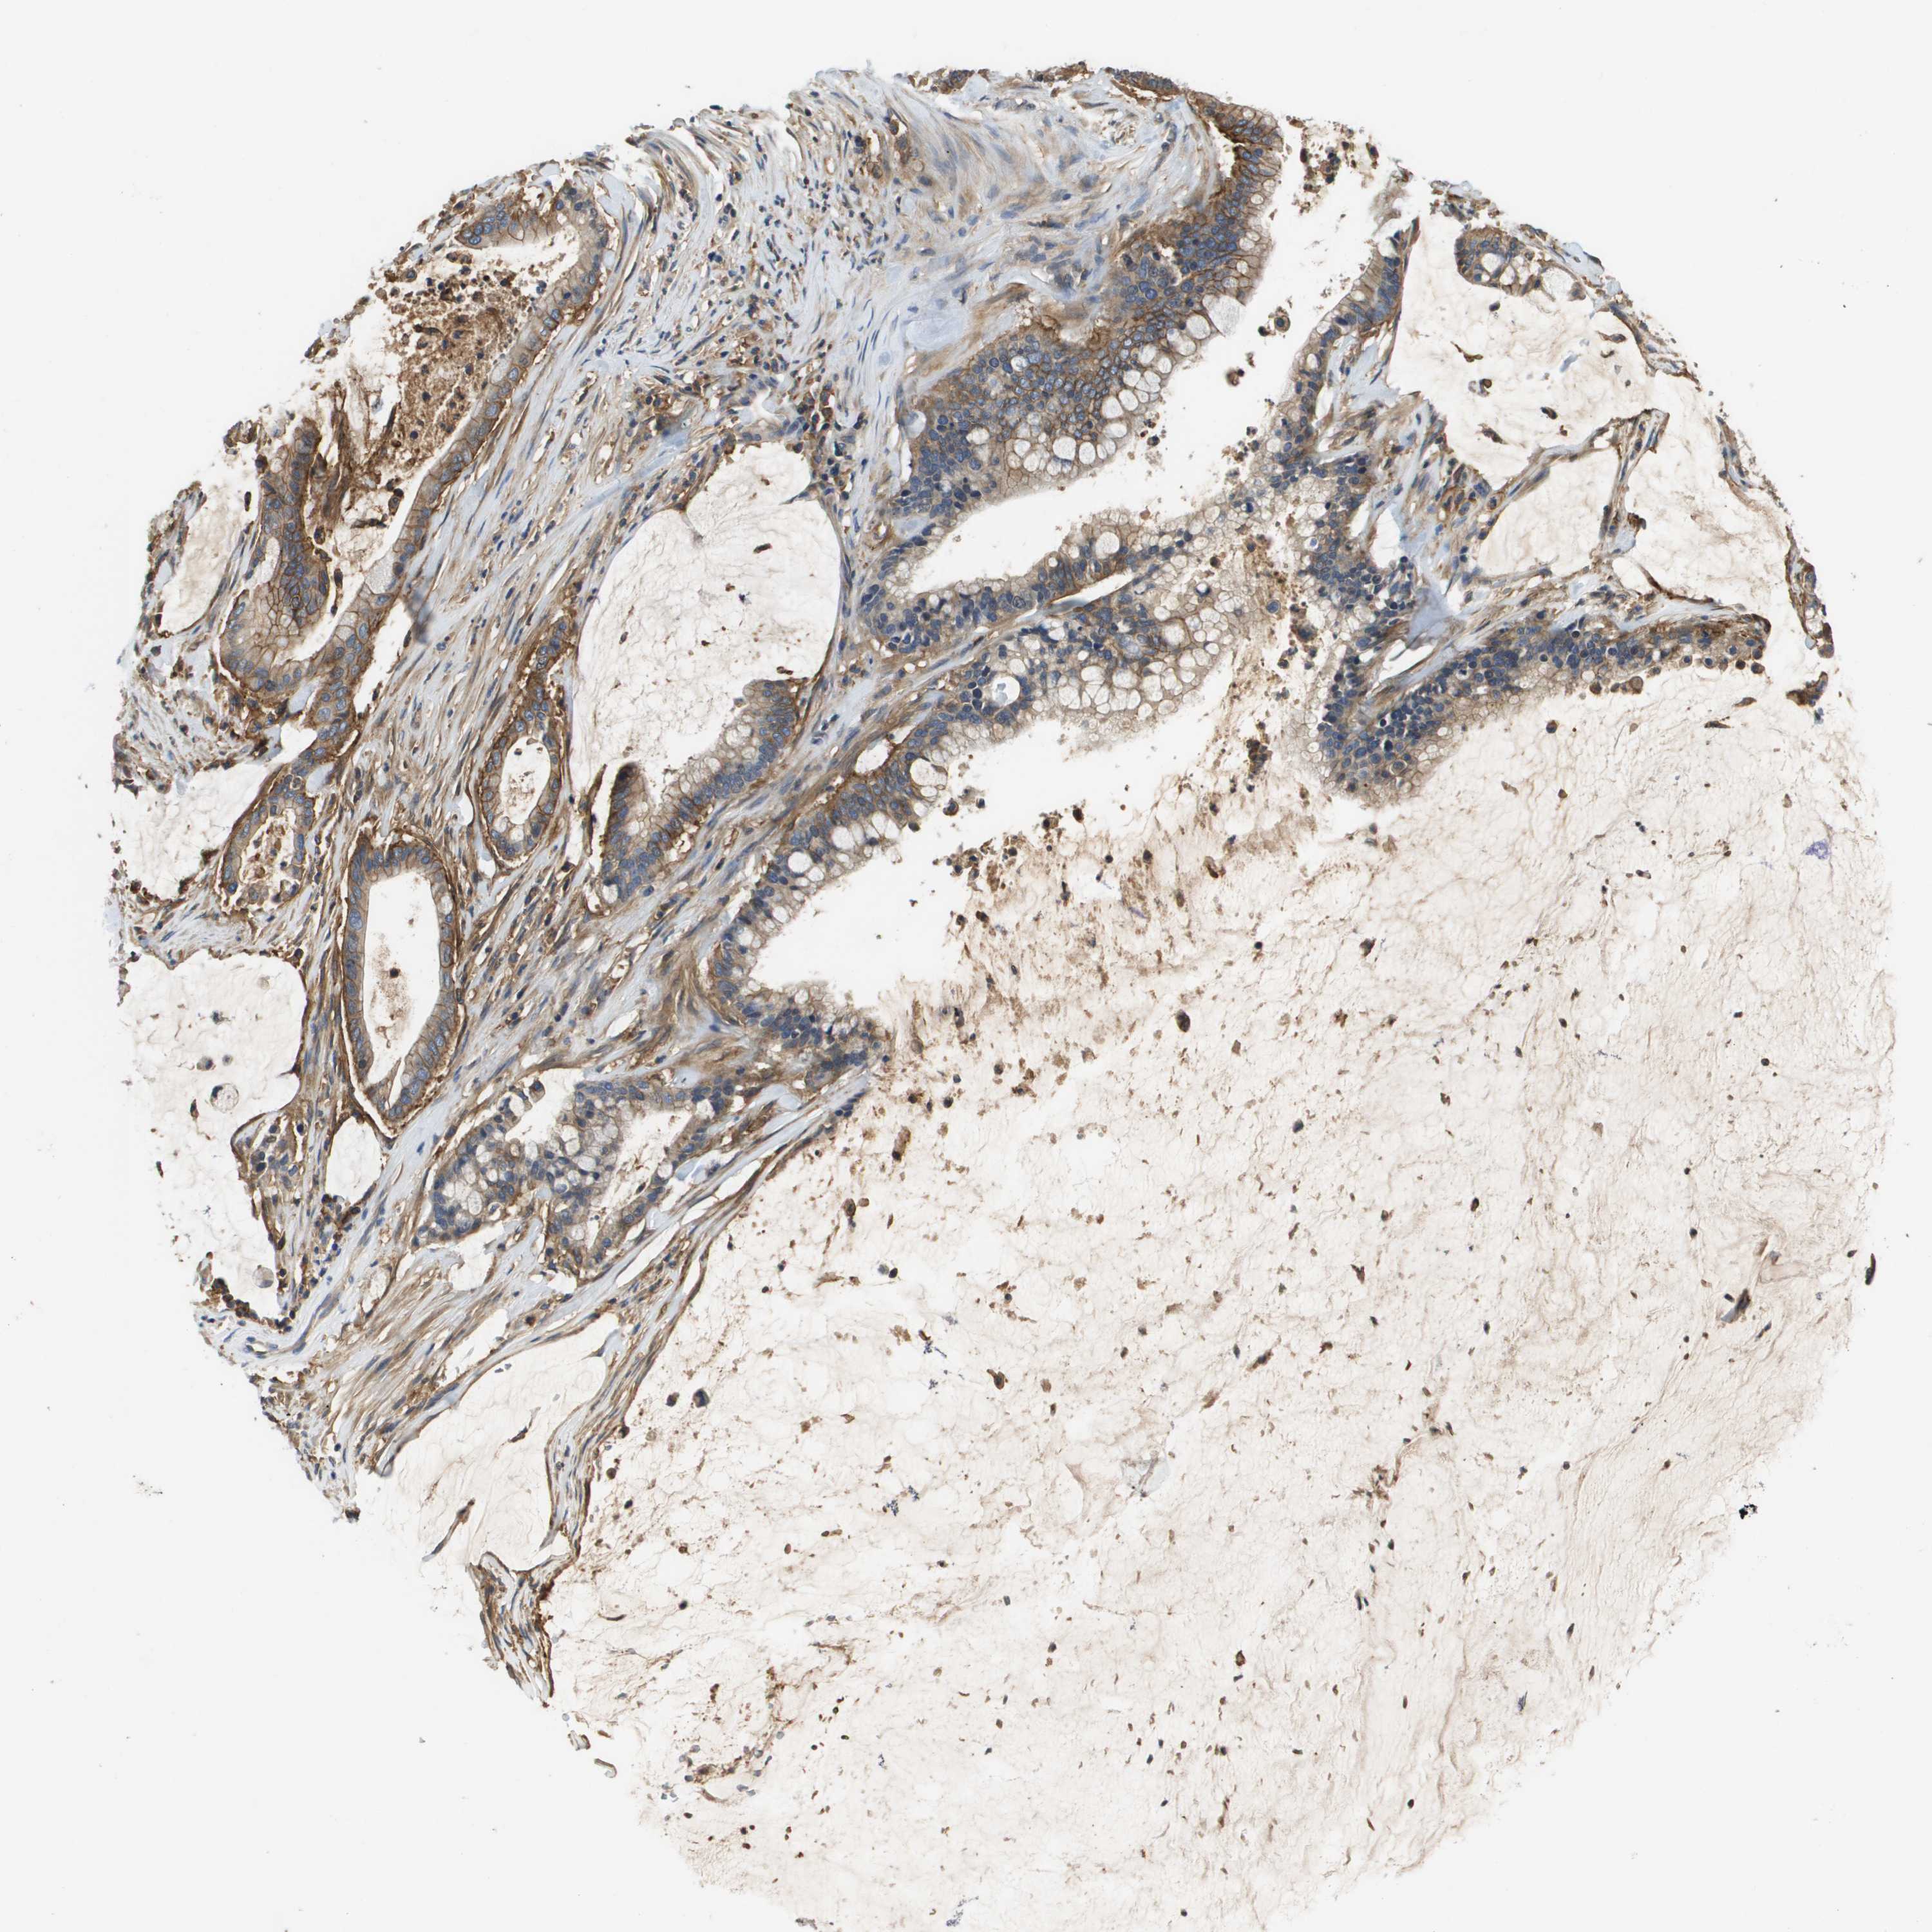

PANCREATIC CANCER - Protein expressioni

A mouse-over function shows sample information and annotation data. Click on an image to view it in a full screen mode. Samples can be filtered based on level of antibody staining by selecting one or several of the following categories: high, medium, low and not detected. The assay and annotation is described here.

Note that samples used for immunohistochemistry by the Human Protein Atlas do not correspond to samples in the TCGA dataset.

Antibody stainingi

Antibody staining in the annotated cell types in the current human tissue is reported as not detected, low, medium, or high, based on conventional immunohistochemistry profiling in selected tissues. This score is based on the combination of the staining intensity and fraction of stained cells.

Each image is clickable and will lead to virtual microscopy that enables deeper exploration of all samples and also displays staining intensity scores, fraction scores and subcellular localization as well as patient and tissue information for each sample.

Antibody HPA021451

Antibody CAB017490

Staining

High

Medium

Low

Not detected

Intensity

Strong

Moderate

Weak

Negative

Quantity

>75%

75%-25%

<25%

None

Location

Nuclear

Cytoplasmic/membranous

Cytoplasmic/membranous,nuclear

Adenocarcinoma, NOS